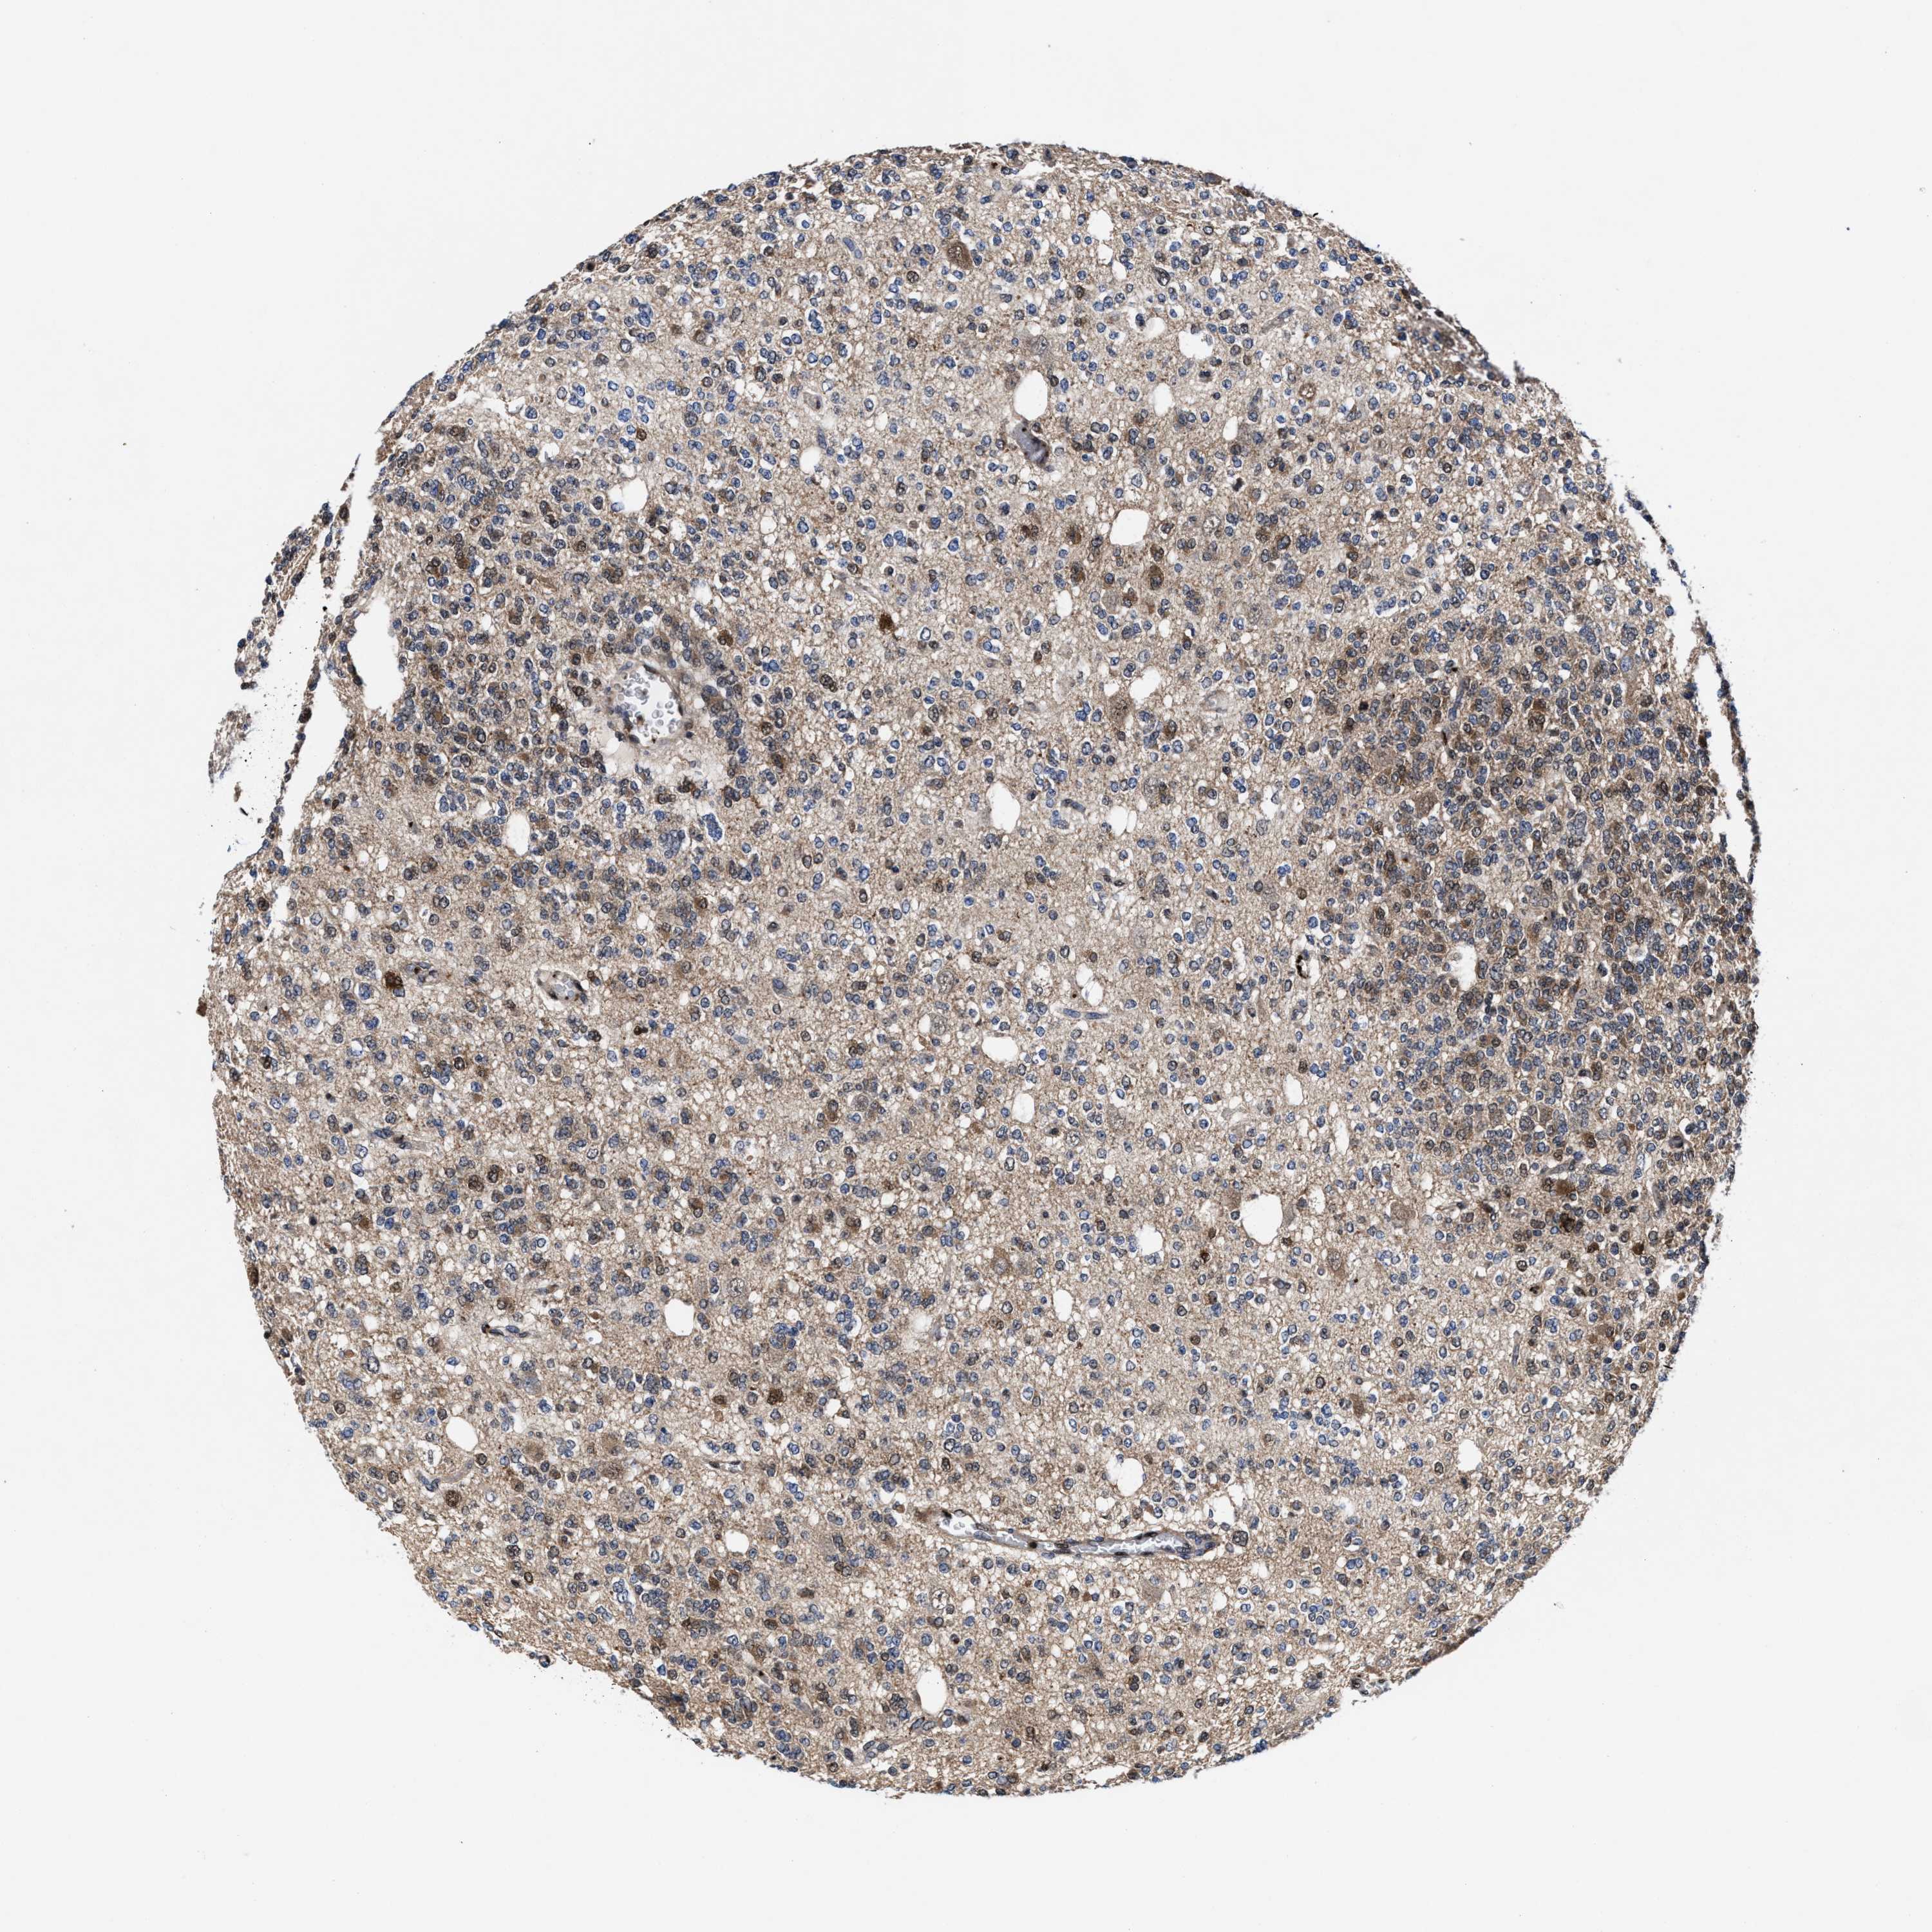

GLIOMA - Protein expressioni

A mouse-over function shows sample information and annotation data. Click on an image to view it in a full screen mode. Samples can be filtered based on level of antibody staining by selecting one or several of the following categories: high, medium, low and not detected. The assay and annotation is described here.

Note that samples used for immunohistochemistry by the Human Protein Atlas do not correspond to samples in the TCGA dataset.

Antibody stainingi

Antibody staining in the annotated cell types in the current human tissue is reported as not detected, low, medium, or high, based on conventional immunohistochemistry profiling in selected tissues. This score is based on the combination of the staining intensity and fraction of stained cells.

Each image is clickable and will lead to virtual microscopy that enables deeper exploration of all samples and also displays staining intensity scores, fraction scores and subcellular localization as well as patient and tissue information for each sample.

HPA022434

HPA022953

HPA022959

HPA028758

CAB007783

Glioma, malignant, High grade

Glioma, malignant, Low grade

Glioblastoma, NOS